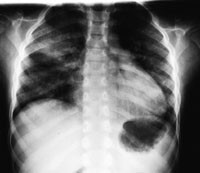

Røntgen thorax i serie med første bilde tatt to timer (fig 1) etter ekstubasjon viste fortetninger forenlig med interstitielt ødem og overlappsatelektase. Ødemet nærmest normaliserte seg i løpet av ni timer (fig 2) og fullstendig i løpet av 48 timer (fig 3), men med bestående atelektase. Pasienten var på dette tidspunkt helt ubesværet. Siste kontrollbilde tatt etter 14 dager var helt normalt.

Lungeødem som utvikles ved forsert inspirasjon har god prognose, men kan være assosiert med tilstander som i seg selv kan være livstruende. Det kliniske bildet varierer fra et fulminant lungeødem med blodtilblandet ekspektorat og klare røntgenfunn, til det mer vanlig forekommende moderate kliniske bildet med uklare røntgenfunn. Vår pasient hadde et moderat klinisk bilde, men røntgenbildene viste klare funn i form av en overlappsatelektase og interstitielt ødem (fig 1 – 3). All den tid pasienten var klinisk upåfallende før operasjonen og oksygeneringen var normal under operasjonen, tror vi lungeforandringene oppstod etter operasjonen. Overlappsatelektasen kan ha oppstått som en følge av det kraftige negative intrapleurale trykk under forsert inspirasjon, en trykkgradient som vil være maksimal mot lungetoppene hos en sittende eller stående pasient. Asymmetrien kan skyldes slimplugging. Derved er atelektasen et resultat av dynamisk lungekollaps som raskt reekspanderer spontant eller ved hjelp av CPAP-behandling. Tidlig bronchusavgang til høyre overlapp gjør denne sårbar for blokade av en tube som sitter like distalt for carina.